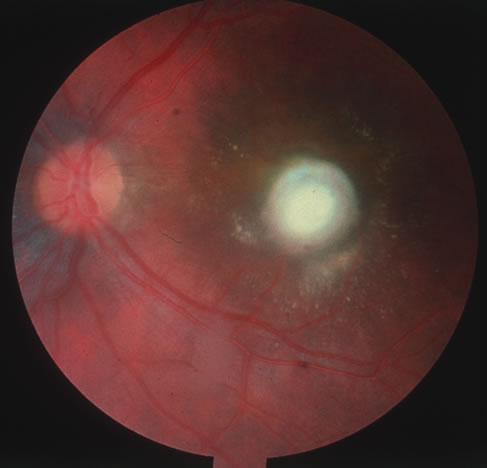

The acute retinal necrosis (ARN) syndrome is most often caused by the herpes zoster virus, although occasionally it may be a result of herpes simplex infection.12 It is typically described in healthy patients although association with immunosuppressed patients has also been described. Granular, nonhemorrhagic areas of retinal necrosis may be observed in the fundus, often rapidly coalescing with resulting blindness often caused by retinal detachment. There is often an associated vasculitis and vitritis. In immunocompromised patients VZV or HSV retinitis may also take the pattern of progressive outer retinal necrosis (PORN) (Fig. 6). PORN differs from ARN in that the former is multifocal, localized to the outer retina, and is less often associated with vasculitis and vitritis.